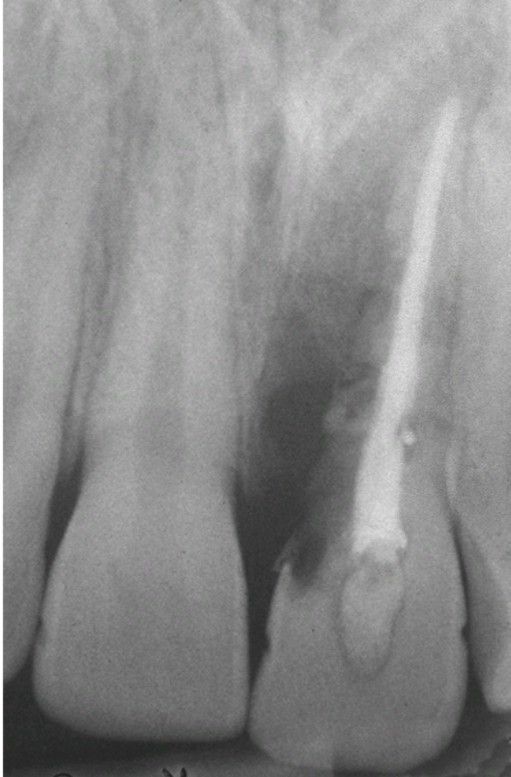

External resorption

Moth-eaten” radiolucent alteration of the maxillary left central incisor. The tooth had been reimplanted after traumatic avulsion.